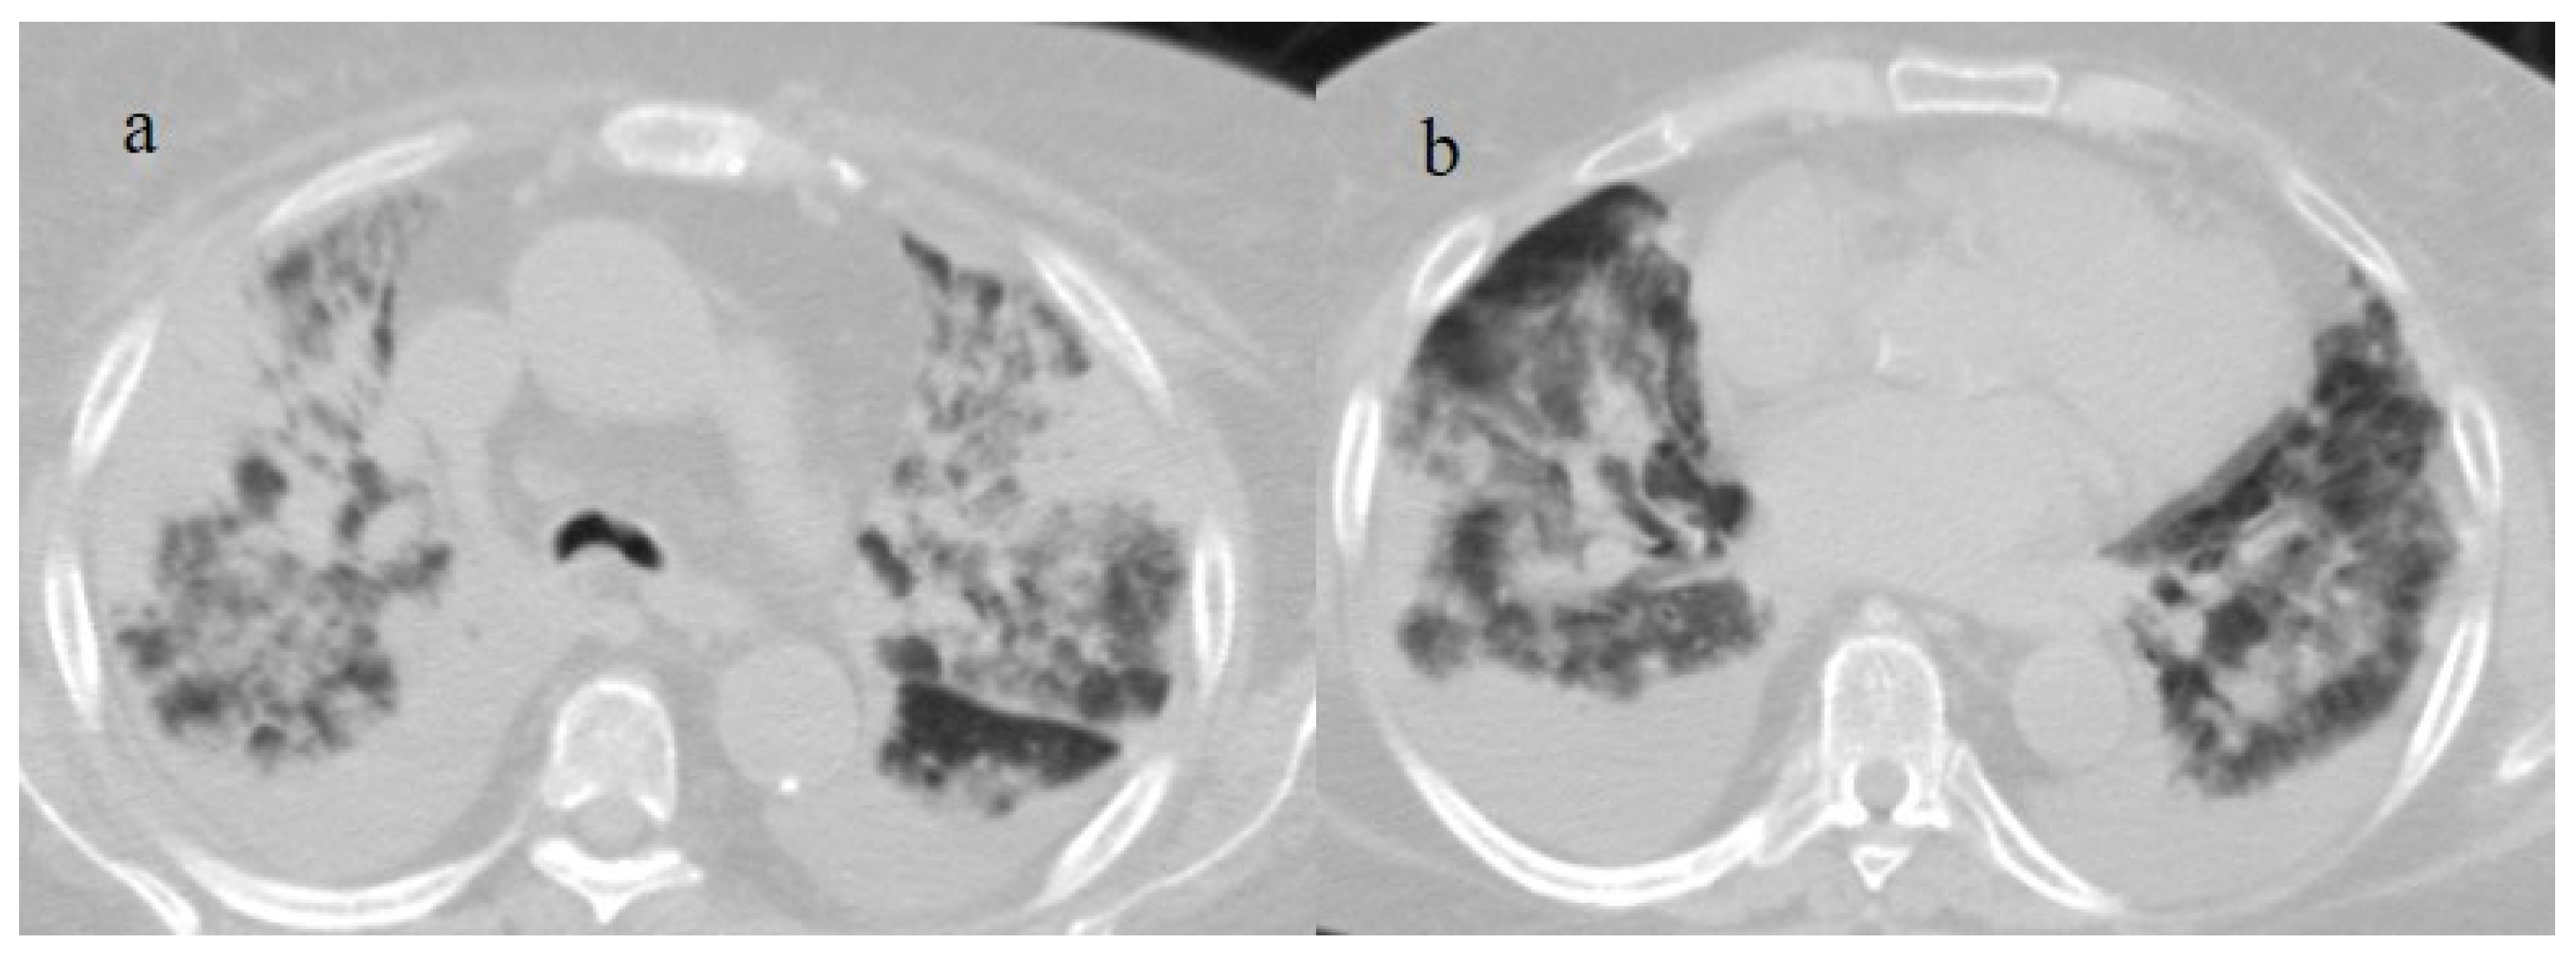

Figure 7.

A 65-year-old patient in breakthrough infection with RT-PCR positivity for SARS-CoV-2 during the Omicron wave (in January 2023) with absence of pneumonia in chest CT as is depicted in image (a,b) on the axial plane.

Figure 8.

Absence of pneumonia in chest CT in images (a,b) in an unvaccinated 40-year-old patient with some comorbidities during the Omicron wave (February 2023).